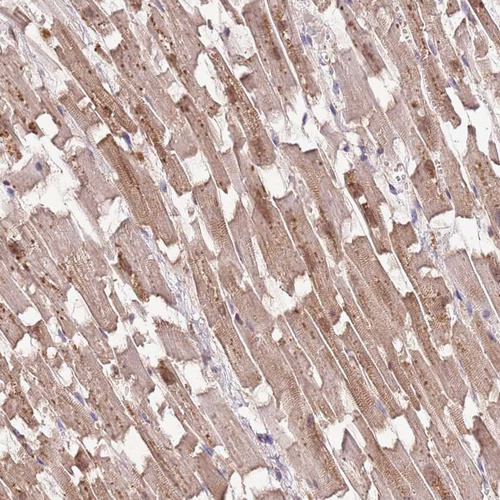

Immunohistochemical staining of human stomach shows strong cytoplasmic-membranous positivity in glandular cells.